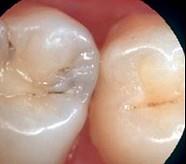

问题 龋好发于牙齿的()

选项 A.自洁区 B.边缘嵴 C.滞留区 D.舌面 E.牙尖

答案 C